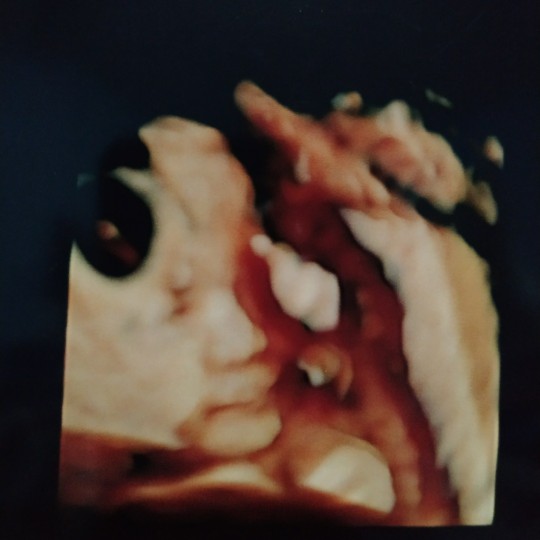

Ini wktu 25week bunda

usia 25 week